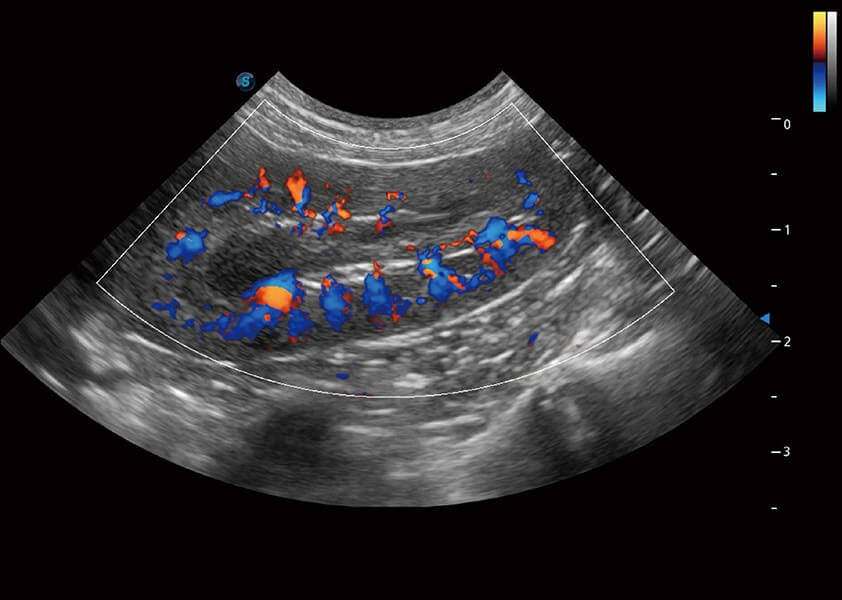

ProPet 60 作为一款高端台式动物超声设备,为动物医生的日常诊断提供了一系列贴合动物临床需求、解决临床实际问题的高级成像功能。凭借全系列高清探头,满足医生对腹部、心脏、生殖、浅表、肌骨等成像的所有需求,切实帮助您提升检查效率,提高诊断信心。

兽用彩色多普勒超声诊断系统

动物是人类最亲密的朋友和最值得信赖的伙伴。MILE米乐集团官网也一直致力于探索动物专用的超声影像解决方案。 全新推出的ProPet系列,是MILE米乐集团官网在动物超声影像智能化、专业化、精准化的一次跨越式革新。动物不能用言语来表述自己的不适,通过超声影像,ProPet系列搭建了动物医生与不同物种沟通的“桥梁”,为动物医生注入了“治愈之力”。